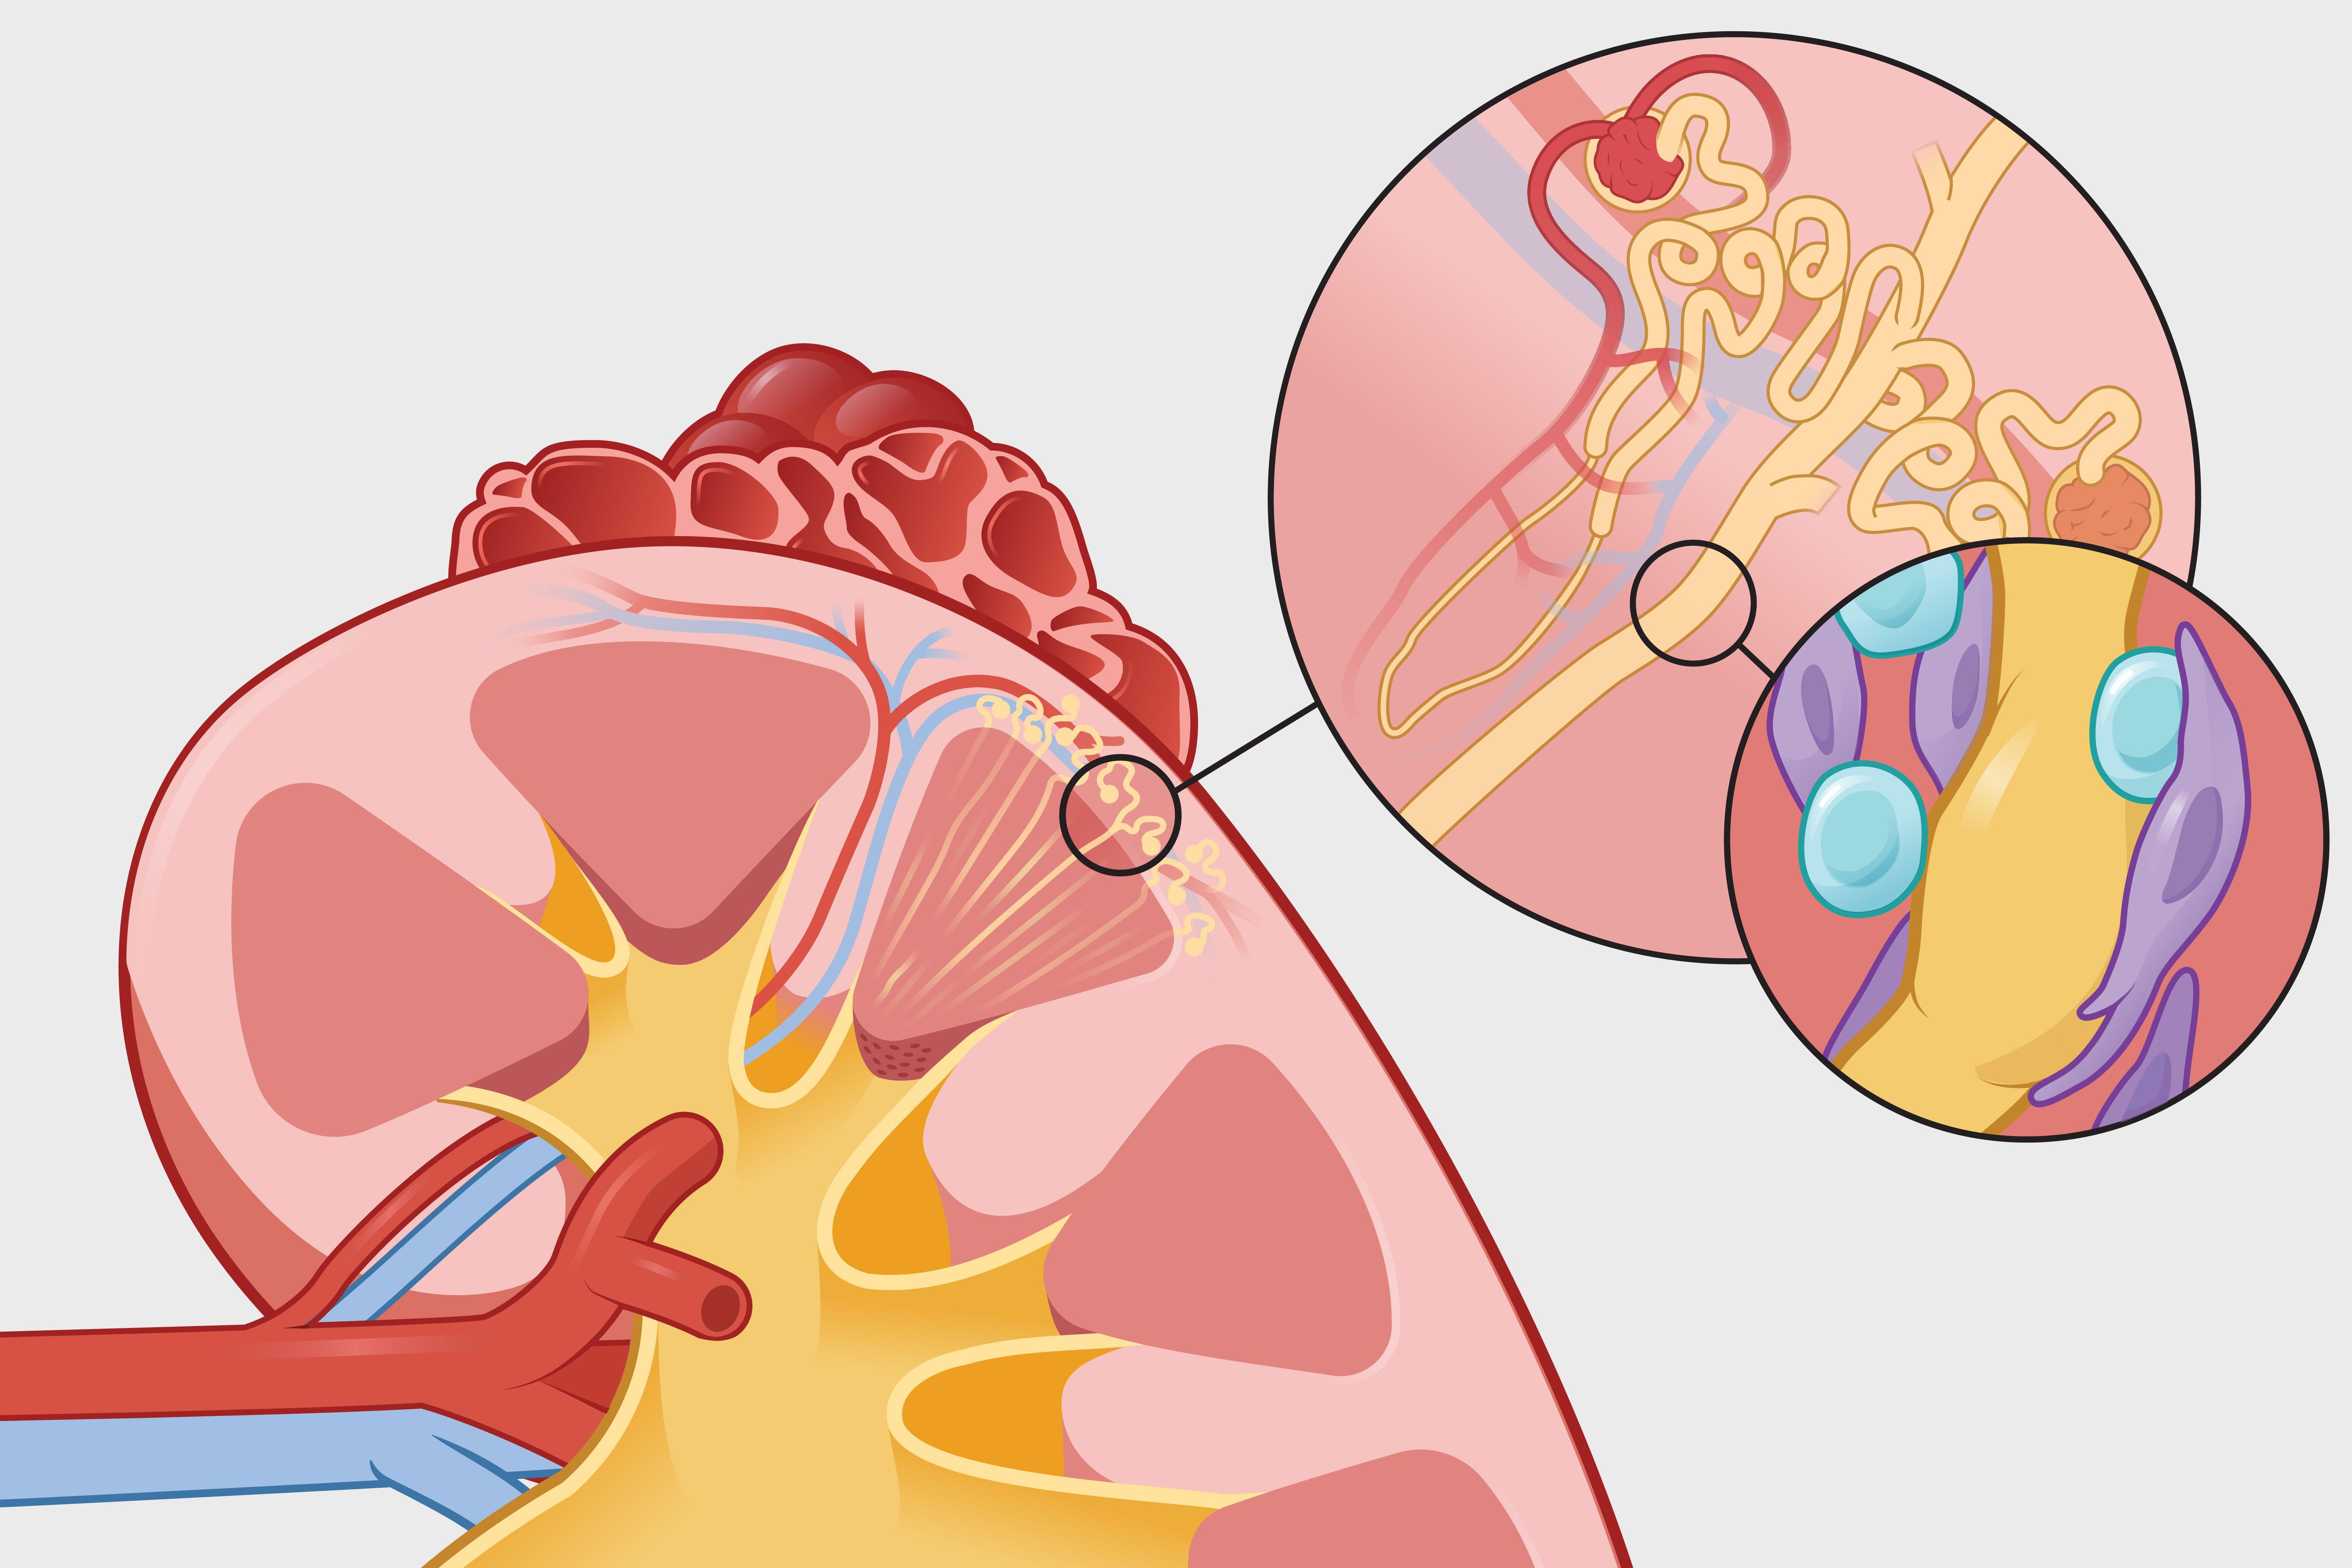

Newly diagnosed kidney patients struggle with heavy burdens, from dialysis to distress

新诊断的肾病患者面临沉重负担,从透析到痛苦

Newly diagnosed kidney patients struggle with heavy burdens, from dialysis to distress

新诊断的肾病患者面临沉重负担,从透析到痛苦

New drugs and treatments transform kidney care

新药物和治疗方法改变肾脏护理

New drugs and treatments transform kidney care

新药物和治疗方法改变肾脏护理

Why there is a distressing rise in kidney disease

肾病为何出现令人担忧的上升趋势

Why there is a distressing rise in kidney disease

肾病为何出现令人担忧的上升趋势

2026-03-17

482词 简单

More kidney patients are having healthy babies after years of discouragement from doctors

越来越多的肾病患者在医生多年的劝阻后生下健康的宝宝

More kidney patients are having healthy babies after years of discouragement from doctors

越来越多的肾病患者在医生多年的劝阻后生下健康的宝宝

2026-03-17

2191词 晦涩